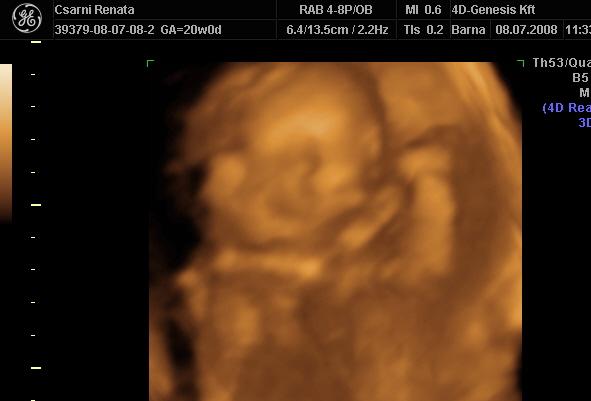

Ma végre voltam ultrahangon :D Nem bántam meg,hogy a genesisbe mentem :) Tényleg nagyon aranyosak.Én a Csillánál voltam és tényleg nagyon aranyos.Jól megnézte a babót.Mindenét meg mutatta.Még a kis ujjacskáit is megszámolta :D De nagyon kis rafinált volt a babó,mert a fejecskéjét elbújtatta a lepénybe és nem nagyon készűlt róla így jó kép.Meghát szinte végig alukált nem lehetett felébreszteni :) És a kezecskéjét mindig az arcocskája előtt tartotta :) Egyszóval jól elbújt :D Végre a nemét is megtudtuk :D Kisfiú :D :D Azt mondta a Csilla,hogy ez 100% :D Így most nagy az öröm a családban :D Rakok fel róla egy képet remélem kivehető valamennyire. Kép Kisfiunk:D

A dokim kicsikét tévedett,mert kiderűlt,hogy 20hetes és 5napos a babó :D Legközelebb a 28.héten megyek megint UH-ra azt mondta a Csilla,hogy akkor már szépen fog látszani a babónk :D De így is megérte elmenni,mert láttuk,hogy megvan mindene és egészséges :D És ez a lényeg.